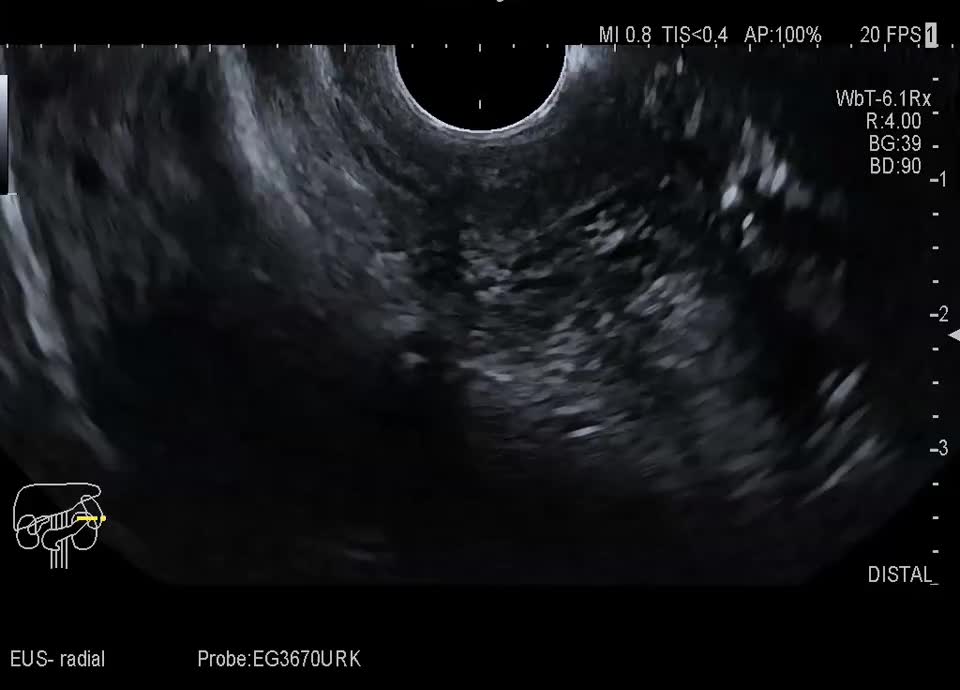

Case

60-year-old female patient with incidental finding of serous cystadenoma one year ago. Current follow-up examination reveals small cystic mass (honeycomb pattern visible on EUS) of constant size in the head of the pancreas/uncinate process. In the transcutaneous B-scan, central echogenic portion (central scar), hypervascularized on color Doppler sonography.